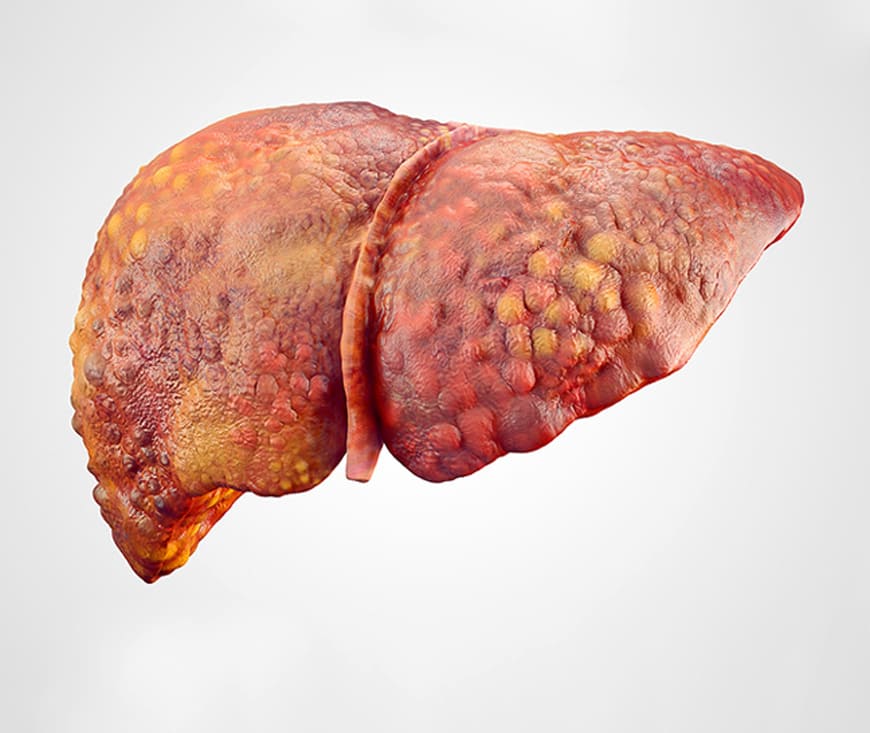

Liver cirrhosis treatment aims to manage symptoms, slow progression, and prevent further liver damage. Medications, lifestyle changes, and a healthy diet are crucial. In advanced cases, a liver transplant may be necessary. Early diagnosis, regular monitoring, and medical care can improve outcomes. Consult a healthcare provider for personalized treatment and care options.